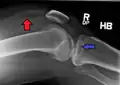

Lipohemarthrosis due to a tibial plateau fracture

A tibial plateau fracture seen on X-ray